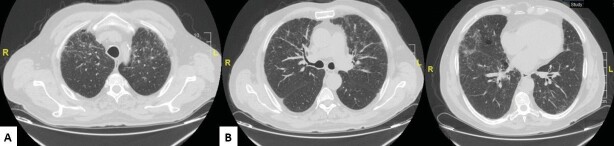

It is important to make the differential diagnosis of restrictive changes associated with hepatic hydrothorax or hepatopulmonary syndrome seen in the later stages of chronic liver diseases and restrictive changes associated with interstitial lung disease. Lymphocytic interstitial pneumonia (LIP) is in the rare idiopathic interstitial pneumonia subgroup of interstitial lung diseases. LIP is a rare disease, and its incidence is unknown. LIP is characterized by infiltration of the alveolar interstitium with lymphocytes, plasma cells, and histiocytes. The etiology of LIP includes idiopathic causes, rheumatological diseases, immune deficiencies, viral infections, and drug-related causes. Chronic liver diseases are also rarely included in the etiology of LIP. A 75-year-old male patient who was followed up for liver cirrhosis presented with dyspnea. He had hypoxemia in the arterial blood gas. In the thorax and abdominal computed tomography, irregular reticulations in bilateral lungs, ground-glass opacities, and scattered air cysts in both lung parenchyma, chronic liver parenchymal disease, splenomegaly, chronic portal vein thrombosis were determined. Clinical and radiological changes in the patient were evaluated in favor of interstitial lung disease. Although histopathological diagnosis could not be made, the patient whose radiological pattern was compatible with LIP was evaluated together with clinical findings and was accepted as lymphocytic interstitial pneumonia. He was evaluated in terms of diseases that could cause LIP. He was accepted as LIP due to chronic liver disease. Although histopathological examination is the gold standard for the diagnosis, a biopsy could not be performed in our case. Radiological and clinical findings were considered sufficient for the diagnosis of LIP. Chronic viral hepatitis and cirrhosis are also present in the etiology of LIP. Our case is presented as an example in the literature because it is a case of LIP due to chronic liver disease, and it is rare.